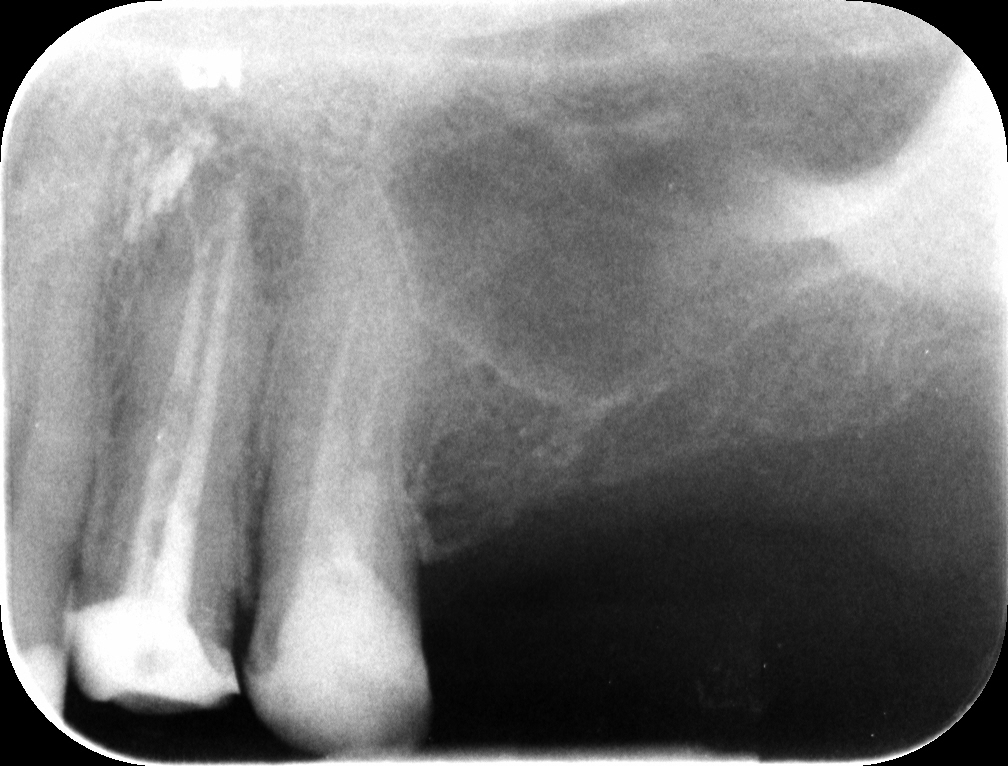

Il paziente si rivolge alla nostra attenzione in seguito a frattura dell’elemento 25 nel suo aspetto palatale; all’esame clinico è visibile la presenza di due perni in fibra di carbonio all’interno del restauro. Viene eseguita una radiografia periapicale (Figura 1) che mostra una terapia endodontica incongrua a carico del suddetto elemento.